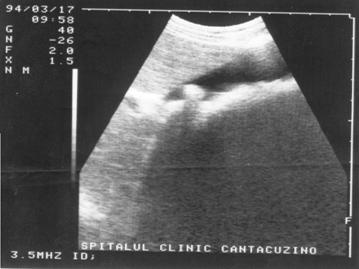

Figura 16. Intarire acustica posterioara la nivelul vezicii urinare.

Figura 17.}ntarire acustica posterioara la nivelul V.B.